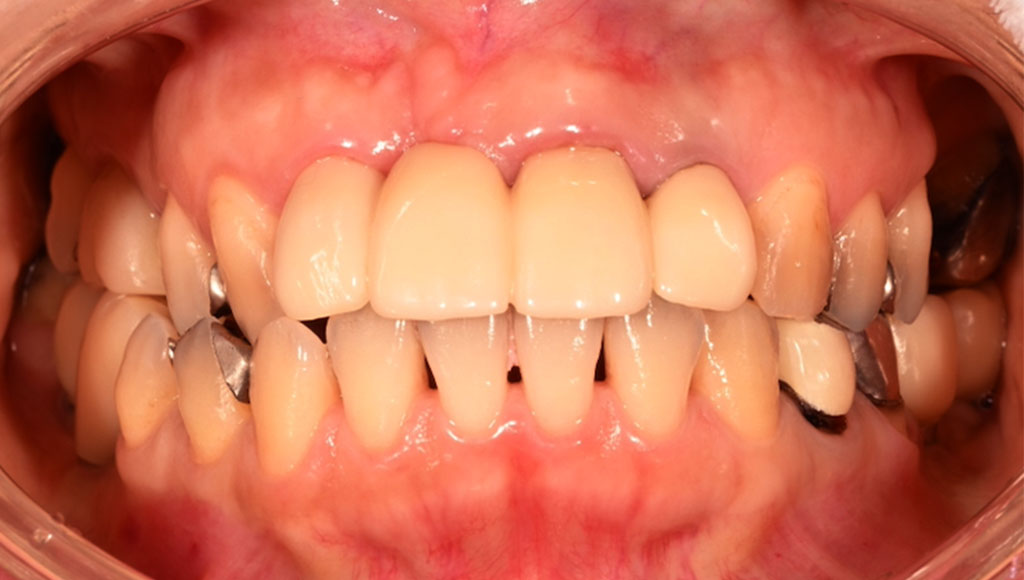

Before1

患者様の主訴

50代女性。横浜市在住。左下45番、右下45番の奥歯の銀歯が見た目に気になりご来院。

診断結果

左下45番、右下45番のインレーを外し、歯の形成を行いジルコニアクラウンをセット

治療内容

ジルコニアクラウンを装着するために元のインレーを外し、歯の形成を行い光学印象(プライムスキャンによる)型取りを行いました。光学印象のデータを元に当院の院内技工室にてデジタル加工を行い、ジルコニアクラウンを作成し、セットを行いました。

治療期間

2回

治療費用

総額:440,000円(税込)

◼️内訳

ジルコニアクラウン:110,000円(税込)/1本×4本

光学印象(プライムスキャン)

リスク・副作用

補綴物の脱落・欠落、咬合違和感、色調補正